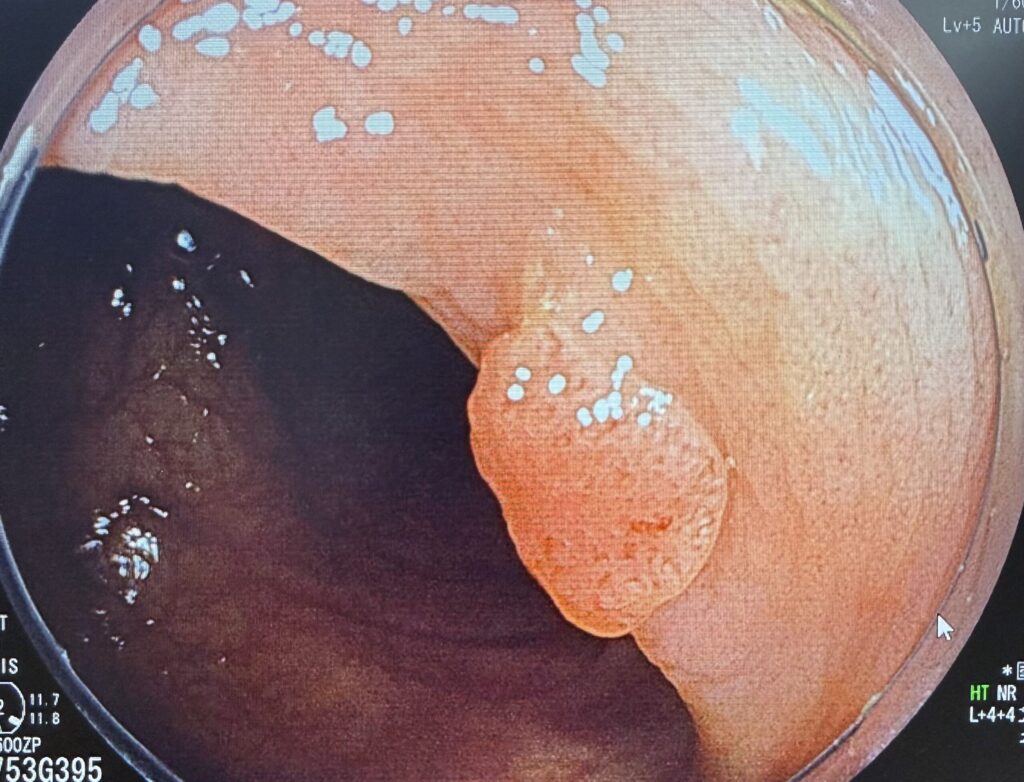

苦痛で体が動いてしまったり、ゲップを我慢して胃に力が入ったりすると、十分な観察ができません。鎮静剤で体の力が抜けていると、胃や腸のヒダをしっかりと広げ、微細な病変まで時間をかけて観察することができます。 これは、早期がんやポリープの発見率向上に直結します。